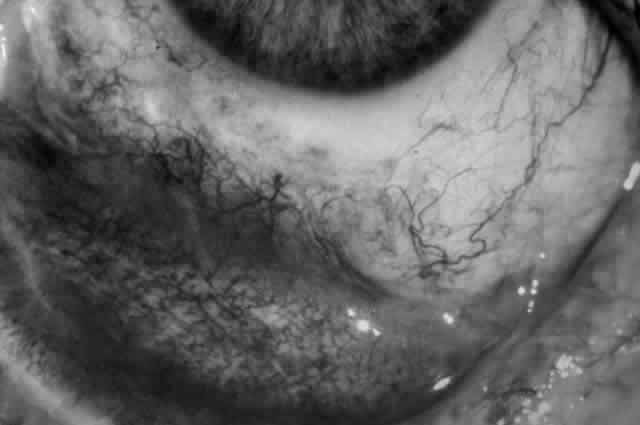

Clinically, the ocular disease in cicatricial pemphigoid (OCP) may present unilaterally in the form of a chronic, recurrent catarrhal conjunctivitis, but it eventually becomes bilateral. Subepithelial fibrosis is characteristic of stage 1 of OCP (Fig. 7). Stage 2 shows fornix foreshortening (Fig. 8), and symblepharon formation is the hallmark of stage 3 (Fig. 9). Stage 4, end-stage disease, is characterized by ankyloblepharon and surface keratinization (Fig. 10). Obstruction of the lacrimal ductules and meibomian gland ducts eventually produces an unstable tear film and progressive sicca syndrome, but it is to be emphasized that OCP is not a dry-eye syndrome until late in the disease course.20 Trichiasis and entropion occur because of the subepithelial fibrosis, with eventual keratopathy, corneal neovascularization, and corneal ulceration and scarring.20

Fig. 7. Stage 1 cicatricial pemphigoid, with cicatrizing conjunctivitis, and fine striae-type areas of subepithelial fibrosis, but without evidence of shrinkage of the conjunctiva.

Fig. 8. Stage 2 cicatricial pemphigoid, with fornix foreshortening and subepithelial fibrosis without frank symblepharon formation.